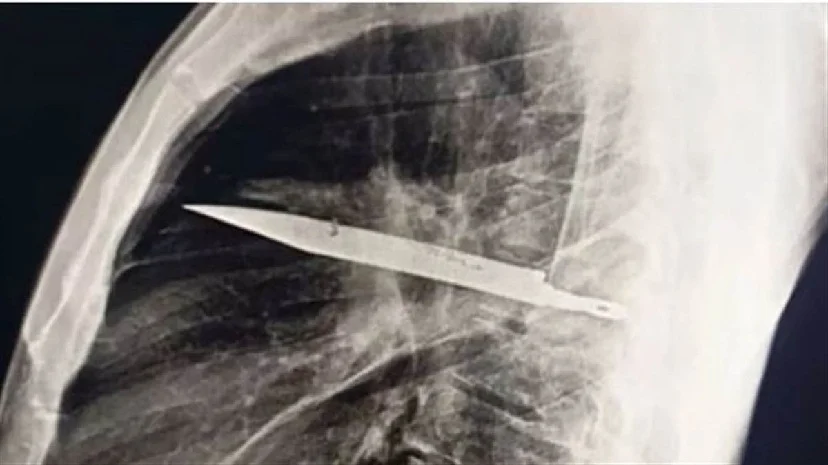

नई दिल्ली, 26 अगस्त : तंजानिया का एक व्यक्ति अपने निप्पल के ठीक नीचे से मवाद निकलने से परेशान था और डॉक्टर के पास गया। डॉक्टर ने जब उसकी जाँच की, तो पता चला कि उसके सीने में चाकू का ब्लेड धँसा हुआ है।

जर्नल ऑफ सर्जिकल केस रिपोर्ट्स में प्रकाशित एक रिपोर्ट के अनुसार, पीड़ित ने डॉक्टरों को बताया कि उसे सीने में दर्द, सांस लेने में तकलीफ, खांसी या बुखार नहीं था, लेकिन उसके दाहिने निप्पल के नीचे से 10 दिनों से मवाद निकल रहा था।

जांच के दौरान सीने में चाकू का ब्लेड मिला।

मवाद की शिकायत के बाद, उनका इलाज दार-ए-सलाम के मुहिमबिली राष्ट्रीय अस्पताल में किया गया, जहाँ डॉक्टरों ने पाया कि चाकू का ब्लेड उनके दाहिने कंधे की हड्डी में घुस गया था और अभी भी उनकी छाती में धँसा हुआ था। रिपोर्ट में कहा गया है कि ब्लेड निकालने के बाद, उनकी हालत में सुधार हुआ और वे 10 दिन बाद घर चले गए। डॉक्टरों का कहना था कि ब्लेड जानलेवा हो सकता था।

8 साल पहले एक झगड़े में चाकू से हमला हुआ था।

31 मई, 2025 की रिपोर्ट में कहा गया है कि आठ साल पहले उन पर एक हिंसक हमला हुआ था जिसमें उनके चेहरे, पीठ, छाती और पेट पर कई बार चाकू से वार किया गया था। घटना के बाद, उन्हें एक क्लिनिक में प्राथमिक उपचार दिया गया और उनके घावों पर टांके लगाए गए। हालाँकि, सीमित संसाधनों के कारण, उन्हें एक्स-रे या सीटी स्कैन के लिए नहीं भेजा गया।